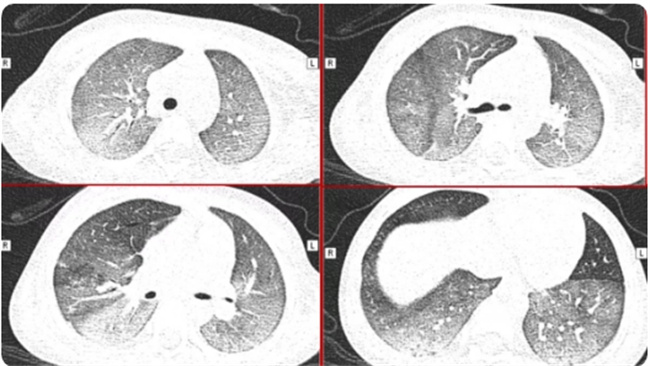

被称之为急性呼吸窘迫性综合症,一般都是在CT检查之下所形成的一种表现,可以看到有一大片的白色状。患者还会有着许多的临床症状,首先白肺患者的血氧饱和度比较低,会有呼吸不畅,会有胸闷气短等现象,而且还可能会有严重的缺氧情况。